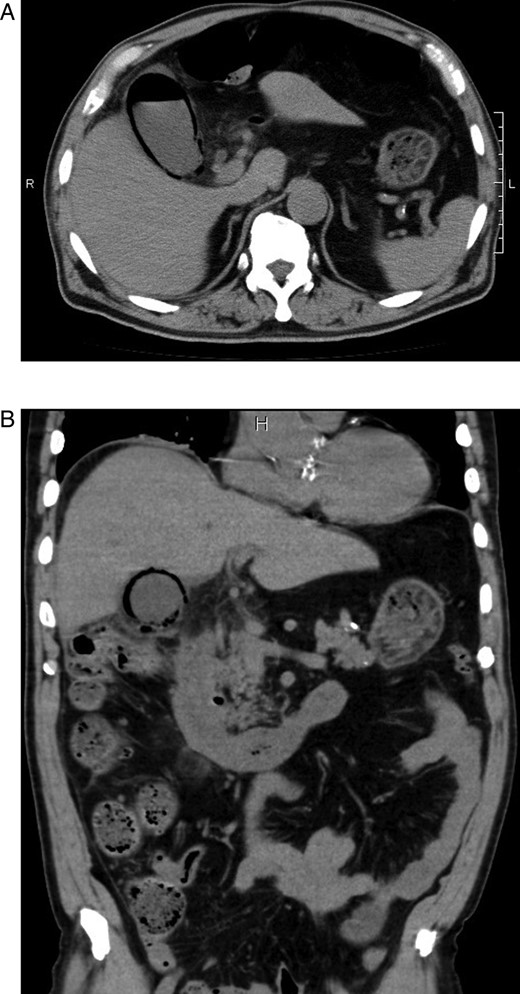

A 78-year-old male was admitted to our hospital for an investigation of vertigo. He had past medical history of diabetes mellitus, hypertension and dyslipidemia. After admission, he developed fever and abdominal distention. A chest X-ray in the up-right position and abdominal computed tomography (CT) were performed. The chest X-ray showed the presence of gas within the gallbladder and in its wall (Fig. 1). The CT scan revealed emphysematous changes in the gallbladder wall and air within the gallbladder (Fig. 2A and B). Therefore, a diagnosis of EC was made. The patient was referred to the Department of Surgery and emergent surgery was performed.

(A and B) Abdominal computed tomographic scans of axial and coronal views revealing emphysematous changes in the gallbladder wall and air in the gallbladder.